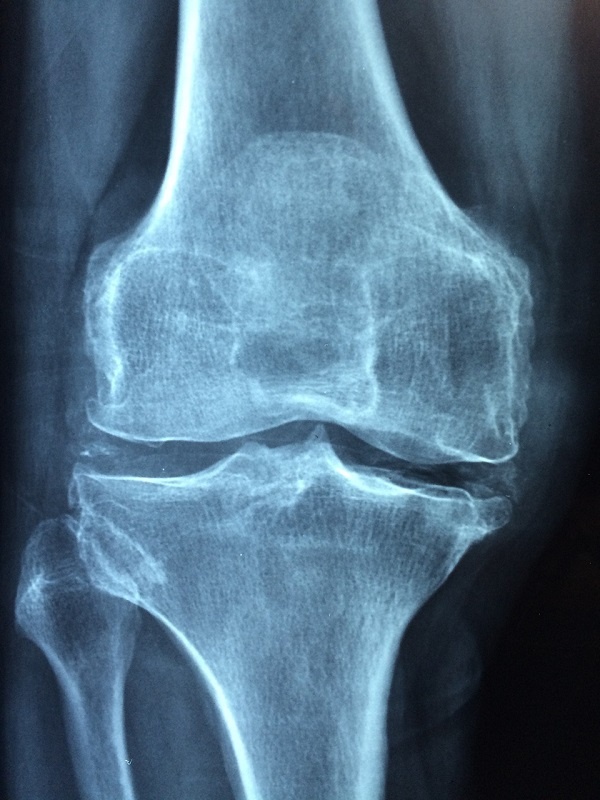

Могут возникнуть осложнения, связанные с острым дефицитом витамина D (рахит у детей ). Эти состояния могут вызвать мягкие и слабые кости и привести к переломам костей, мышечной слабости, боли в костях и даже постоянным деформациям костей, если не заниматься лечением.

• Боль в спине или суставах.